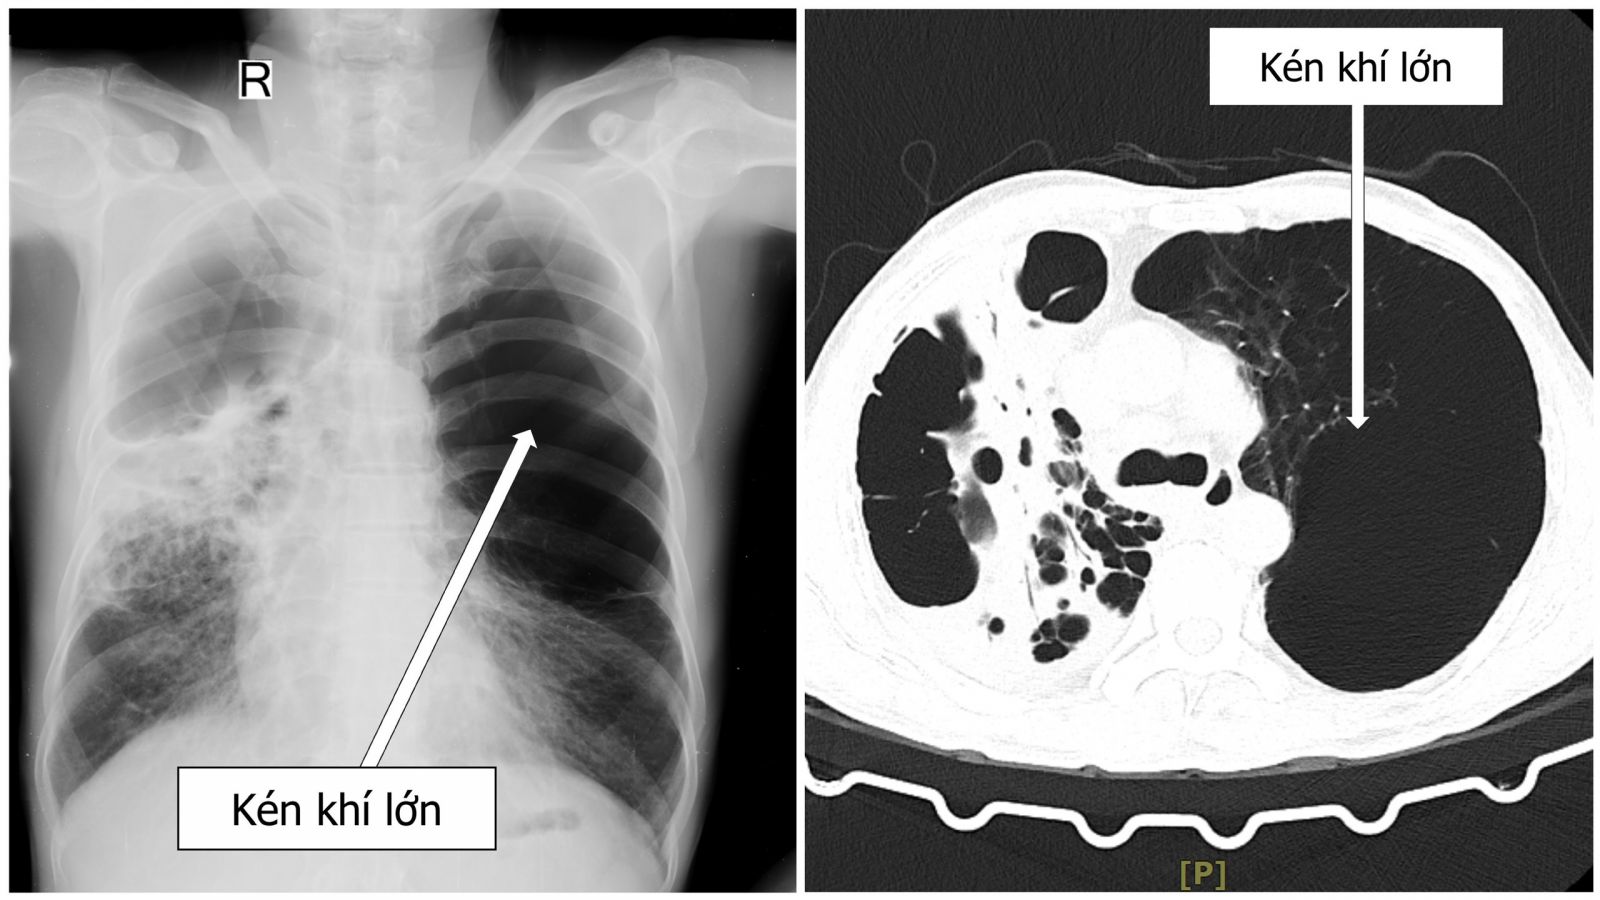

Tại Bệnh viện Đa khoa Trung ương Quảng Nam, kết quả chụp CT Scan cho thấy bệnh nhân có kén khí phổi kích thước lớn chiếm 2/3 thể tích phổi, gây xẹp phổi trái kèm kén khí lớn chiếm một nữa lồng ngực phải phối hợp dãn phế quản và viêm phổi phải. Sau khi hội chẩn chuyên khoa bệnh nhân được các bác sĩ chỉ định phẫu thuật nội soi hỗ trợ (VATS) cắt kén khí phổi một kỹ thuật hiện đại, xâm lấn tối thiểu nhưng mang lại hiệu quả cao trong điều trị kén khí phổi.

Hình ảnh kén khí phổi lớn của bệnh nhân H.Đ.H. Ảnh: BS cung cấp